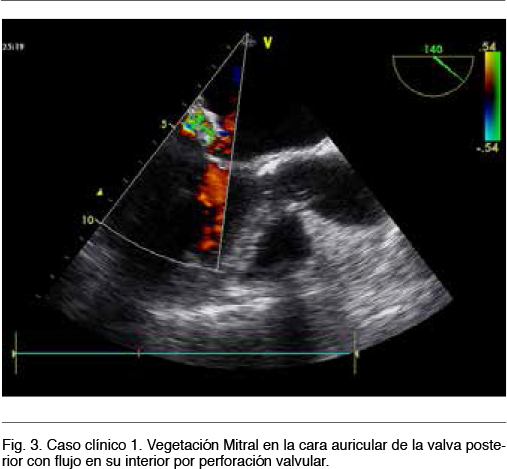

Ecocardiograma transesofágico (ETE): En la válvula Mitral a nivel de la comisura posterior presenta masa hiperrefringente de 22x8x10 mm con sector fijo adherido a cara auricular y sector móvil que protruye hacia y desde el ventrículo izquierdo (VI), compatible con vegetación valvular. Insuficiencia mitral leve. FEVI 60%

Nuevo ETE: FEVI 45%. Vegetación mitral perforada a nivel de la valva posterior con insuficiencia severa. Pequeña vegetación sobre válvula aórtica. Figura 3